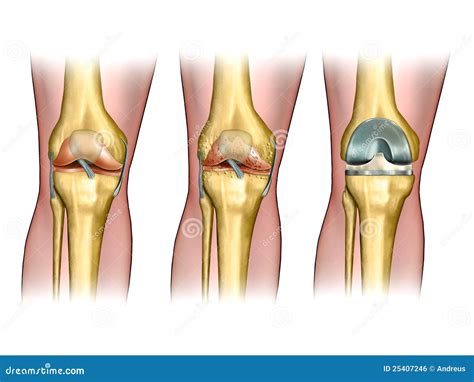

Here is an example of knee replacement images that highlight the benefits of the procedure:

Knee Replacement Benefits

📸 Note: The images above are for illustrative purposes only. Always consult with a healthcare provider for personalized information.

Knee replacement surgery, also known as knee arthroplasty, involves replacing the damaged parts of the knee joint with artificial components. This procedure is typically recommended for individuals with severe arthritis, injury, or other conditions that cause chronic knee pain and limit mobility. The primary goal of knee replacement surgery is to relieve pain, improve function, and enhance the overall quality of life.

• Bone Preparation: The damaged bone and cartilage are removed, and the bone surfaces are prepared to receive the implants.

• Implant Placement: The artificial components are placed and secured with cement or other fixation methods.